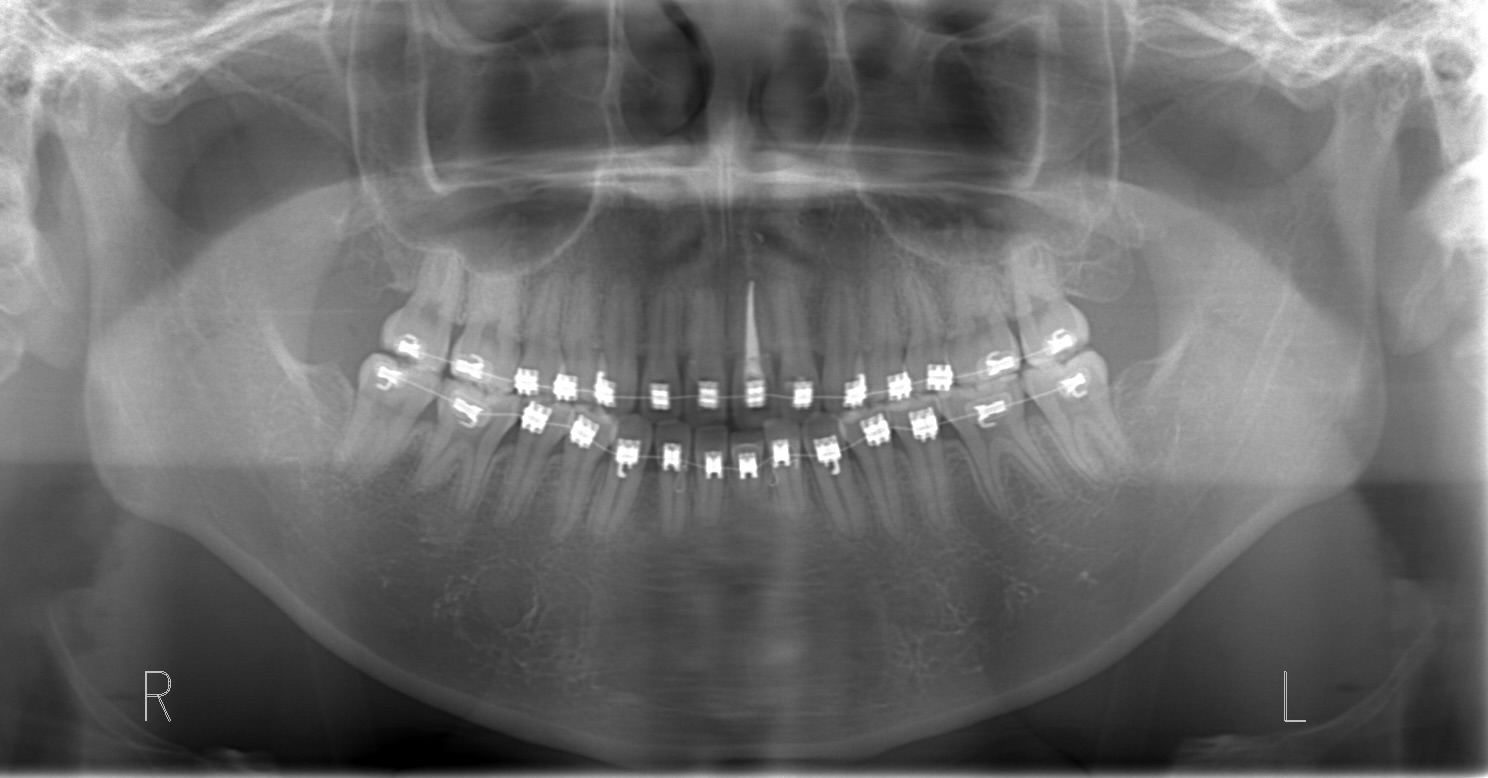

セファロレントゲンにより親知らずの存在を確認するも13歳でありすぐに抜歯することは不可能と判断。

親知らずが抜ける位置まで移動してきたため、矯正治療しながら親知らずの抜歯も行う。

親知らず抜歯後

親知らずに押され臼歯部での噛み合わせが高くなってしまい、前歯が噛まなくなってしまっている。

親知らずを抜歯してそのスペースを利用して臼歯部を圧下しつつ、前歯の噛み合わせを近づけていく。